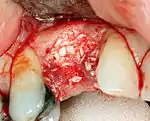

Hard tissue (bone) reconstruction

Bone grafting is necessary when there is a lack of bone. Also, it helps to stabilize the implant by increasing survival of the implant and decreasing marginal bone level loss.[43] While there are always new implant types, such as short implants, and techniques to allow compromise, a general treatment goal is to have a minimum of 10 mm (0.39 in) in bone height, and 6 mm (0.24 in) in width. Alternatively, bone defects are graded from A to D (A=10+ mm of bone, B=7–9 mm, C=4–6 mm and D=0–3 mm) where an implant's likelihood of osseointegrating is related to the grade of bone.[44]: 250

To achieve an adequate width and height of bone, various bone grafting techniques have been developed. The most frequently used is called guided bone graft augmentation where a defect is filled with either natural (harvested or autograft) bone or allograft (donor bone or synthetic bone substitute), covered with a semi-permeable membrane and allowed to heal. During the healing phase, natural bone replaces the graft forming a new bony base for the implant.[39]: 223

Three common procedures are:[44]: 236